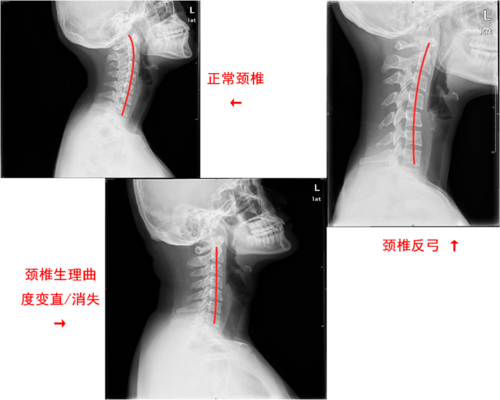

颈椎曲度变直了还能恢复吗做到这4点就不难

颈椎生理曲度变直消失怎么回事

正常颈椎图片

正常颈椎和不正常图片